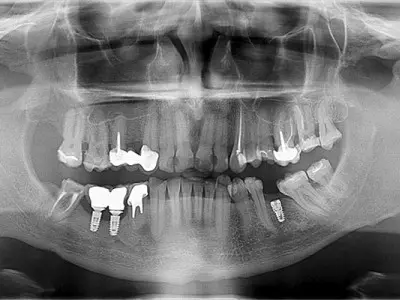

W tym wydaniu m.in: zatrzymane jedynki stałe, leczenie stomatologiczne dzieci w znieczuleniu ogólnym finansowanym przez NFZ, leczenie zapalenia przyzębia metodą niechirurgiczną, relacja drobnoustroje – przyzębie.

W tym wydaniu m.in: skojarzone leczenie dużej zmiany okołowierzchołkowej, miejsce nimesulidu w leczeniu bólu poekstrakcyjnego, materiał Activa BioActive, odbudowa braków międzyzębowych w szczęce, Warsaw Dental Medica Show 2025.